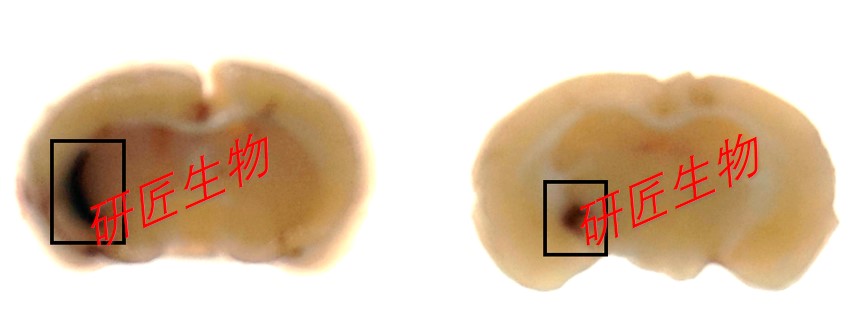

健康成年wistar大鼠,体重250-300g,禁食12h,禁水6h,水合氯醛麻醉后,将大鼠固定在立体定位仪上,行头皮正中切口,剥离骨膜,于前囟后1mm,中线偏左3mm钻直径1mm的小孔,用固定在立体定位仪上的微量注射器沿孔垂直缓慢进针,进针深度6mm(左侧尾状核的位置),缓慢注入胶原酶VII0.5U(用生理盐水配成1U/uL),注药后留针10分钟。

推针,骨腊封闭骨窗,缝合皮肤,回笼饲养,给予正常进食进水,室温控制在25度左右。术后观察神经症状体征。

文献和实验一、技术简介: 脑出血(cerebral hemorrhage)是指非外伤性脑实质内血管破裂引起的出血,占全部脑卒中的20%~30%,急性期病死率为30%~40%。目前实验造模的方法主要有脑立体定位注射自体血或者胶原酶,我公司有多年脑出血造模经验,可以满足实验要求。 脑缺血再灌注损伤(cerebral ischemia-reperfusion injury)是指脑缺血致脑细胞损伤,恢复血液再灌注后,其缺血性损伤反而进一步加重的现象。建立理想的脑缺血再灌注损伤动物模型是脑血管病研究的基础

artery occlusion 的缩写形式,中文意思为中脑动脉栓塞。大脑中动脉栓塞模型并不是把线栓插进大脑中动脉,而是经颈内动脉入颅并插入大脑前动脉,从而阻塞来自栓塞侧的大脑前动脉的血供,以及堵塞接受后交通动脉血供的的颈内动脉颅内段。 ICH造模:ICH是intracerebral hemorrhage的缩写形式,中文意思为脑出血。目前主要有四种方式用于脑出血动物模型的制备:微球囊充胀法、细菌胶原酶注入法、自体血注入法和自发性脑出血模型。 TBI造模:TBI是traumatic brain injury